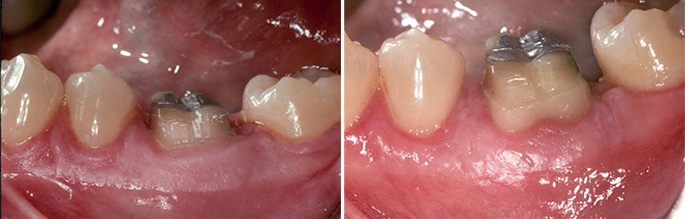

2. Gums That Look Like They're Pulling Away from Your Teeth

If your teeth look longer than they used to, or if you can see the yellowish root surface near the gumline, your gums may be receding. Gum recession is a hallmark sign of periodontal disease — though it can also be caused by aggressive brushing, orthodontic movement, or thin gum tissue.

Recession exposes the tooth root, which has no enamel protection. This leads to sensitivity, especially to cold or sweet foods, and significantly increases the risk of root decay. Receded gum tissue does not grow back on its own — but it can be restored with a gum grafting procedure performed by a periodontist.

5. Swollen, Red, or Tender Gum Tissue

Healthy gums are firm and pale pink. Gums that are red, puffy, or tender to the touch are inflamed — a response to bacterial infection in the tissue. This can occur around individual teeth or affect the entire gum line.

Some patients notice this most during eating, when gum pressure causes discomfort. Others only notice the discoloration when looking closely in the mirror. Either way, inflamed gum tissue is not cosmetic — it reflects active infection that will progress without treatment.